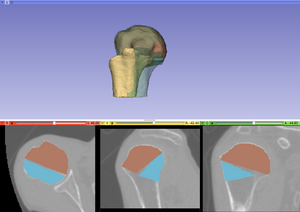

After the first step of the reconstruction is finished and user can inspect the intermediate result. 2D and 3D views will be update according to the calculated transformations. At this point the user, the following scenarios are possible: 1) Good registration - Accept registration without performing further registration (fine tuning part will be skipped). By pressing the "Start fine tuning" button the second part of the reconstruction process in which the fragments will be aligned against each other (without using the reference bone) will be started. The parameters for this step can be changed in the corresponding parameter tab ("Parameters for fine tuning") After the calculations for the fine tuning step are finished, the last tab will be opened ("Result step 2"). Again 2D and 3D views will be updated accordingly and the same 4 scenarios as in the previous step are possible.  Updated 2D and 3D views after final step of reconstruction. Note that the visible gaps are due to missing bone that has been "simulated" in this (toy) example. This view was generated using a wireframe representatioin of the fragments in combination with a volume rendering of CT dataset of the (healthy) reference bone